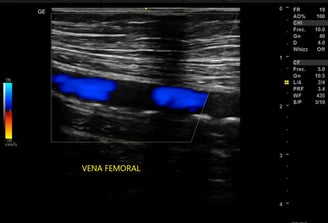

Diagnóstico a domicilio para visualizar el flujo sanguíneo y detectar obstrucciones en vasos sanguíneos.

Diagnóstico por imágenes para visualizar el flujo sanguíneo y detectar obstrucciones en vasos sanguíneos.

Detecta obstrucciones y estrechamientos en vasos sanguíneos, ayudando en el diagnóstico de condiciones médicas.

Visualiza el flujo sanguíneo y detecta obstrucciones vasculares.